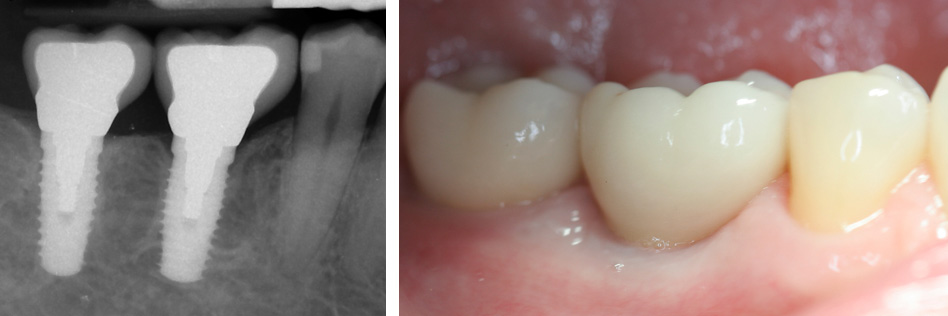

Posterior Dental Implants (Back teeth)

The vast majority of posterior dental implants are predominantly facilitating function and health. The place of back teeth is essential, because the majority of the chewing function is on the back teeth. The major benefits include preservation of the jaw bone, preservation of adjacent teeth structure and eliminating the need for a bridge and prevention of facial collapse which prevents premature aging. Premature aging is prevented by maintaining esthetic dimensions of the dental facial spatial complex, the vertical dimension from the tip of your nose to your chin (occlusion)- bite. The loss of teeth accentuates this thus deepens the folds in your face.